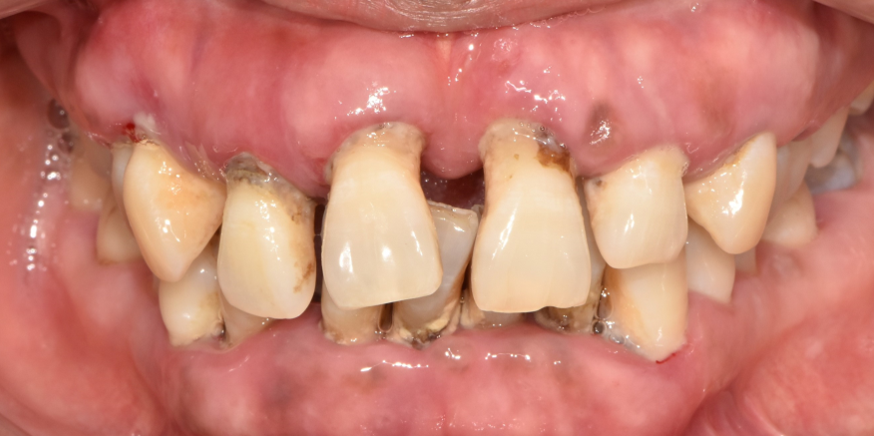

낙성대역 치과 에서 오늘 소개해 드릴 케이스는 앞니가 몽땅 빠져버릴 것 같다며 저를 찾아오셨던 환자의 증례입니다.

사진을 보며 하나씩 설명드리겠습니다.

사진을 보고 어떤 걸 느끼셨나요? 깔끔하고 좋은 인상을 줄 수 있을까요?

그렇진 않습니다. 심미성이 확연히 떨어지는 것을 볼 수 있죠. 안타깝지만 아무도 좋은 쪽으론 생각하지 않을 겁니다.

심미뿐만 아니라 절단, 교합의 기능을 할 수 없게 되는데요.

낙성대역 치과 에서 하루빨리 해당 문제를 개선해 드려야겠습니다.